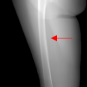

In this section, we provide qualitative and quantitative results of the two proposed diffusion-based methods and compare them with the baseline U-Net model. The first column of Fig. 3 showcases six randomly selected conditions: (a0)-(c0) show contour segmentations, and (d0)-(f0) denote segmentations containing contour and bones. In Fig. 3 (a1)-(f1), the images generated by U-Net contain blurred fine details in locations where bones overlap, despite maintaining the given shape, as highlighted by the red circle. In contrast, the results from CSM appear more realistic than the U-Net. However, their quality decreases with introduced constraints, as indicated by the red arrow in Fig. 3 (d2) and (f2). The results from CTM not only achieve nearly the same level of fineness as the labels but also provide reasonable results with respect to the given conditions as illustrated in the fourth column.

Table I summarizes the quantitative results averaged across all testing data. The evaluation metrics include mean absolute error (MAE) and peak signal-to-noise ratio (PSNR). We observed that CTM performs substantially better than U-Net and CSM under both segmentation-based conditions, and CSM performs worse than the U-Net.

Unlike the U-Net which learns a mapping function between input and output, the diffusion models can implicitly capture the underlying data distribution from the training data and then sample it, preventing the loss of fine details on the pixel level. However, in CSM, conditions are incorporated only at the first sampling step while being perturbed, which results in imprecise conditional information. Instead, CTM provides an estimated score function of the conditional distribution for each sampling step, accommodating both reliability and realism. Nonetheless, presently generated X-ray images only encompass independent 2D conditional information, which may introduce geometric inconsistencies between a set of projections. Future research will focus on modeling 3D probabilistic distributions with the provided 2D conditions to enable CT reconstruction from the generated projections. In addition, clinical datasets will also be incorporated.